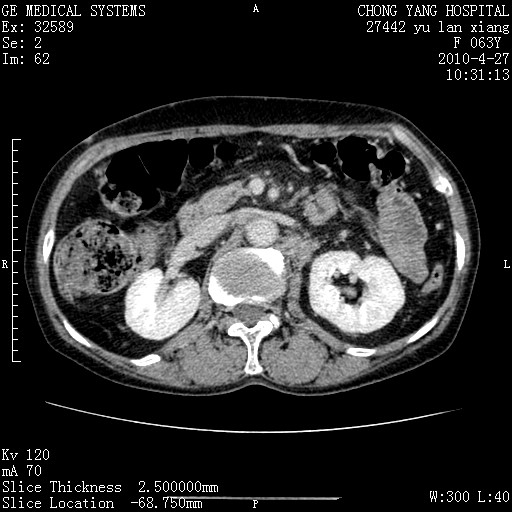

标题: CT26066:F63Y 上腹正中压痛半月,CA199:7400u/ml,MR示胰腺炎伴 [打印本页]

胰腺癌侵犯腹腔动脉干-分支、胃壁、左侧膈肌伴胰周及腹膜后淋巴结转移、胆囊切除术后。

胰腺癌侵犯腹腔动脉干-分支、胃壁、左侧膈肌伴胰周及腹膜后淋巴结转移、胆囊未显影。